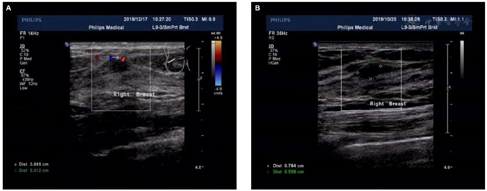

基线信息收集后,研究对象参加后续健康体检。良性乳腺结节是乳腺超声检出的一种乳腺三维病灶,包含乳腺囊肿、实性或混合性肿块,导管内肿块及乳腺占位(图1)。收集良性乳腺结节超声成像特征,包括结节的位置、数量、大小、回声、成分、边缘、形态、钙化、血流、导管扩张情况、对侧乳腺有无结节等。当双侧乳腺有多发结节,则取BI-RADS分级最高的一枚结节入选本研究,若多发结节BI-RADS分级相同,则取直径最大者入选本研究;随访期间,记录结节的前后对照变化,采用电子卡尺测量结节最大径(单位:mm)。将乳腺结节按最大直径(<8 mm或≥8 mm)、数量(单发或多发)、边缘(不光滑或光滑)、形态(不规则或规则)、成分(囊性、混合性、实性)、钙化(有或无)、血流(血流丰富或不丰富)、导管扩张情况(有或无)、对侧结节(有或无)进行分类。由经验丰富的超声科医生使用5~12 MHz的线性探头(OXANA 2,西门子)和5~36 MHz线性探头(iu 22,飞利浦)对所有研究对象进行乳腺超声检查及后续评估。

注:A为首次检出的良性乳腺结节,B为良性乳腺结节增长后